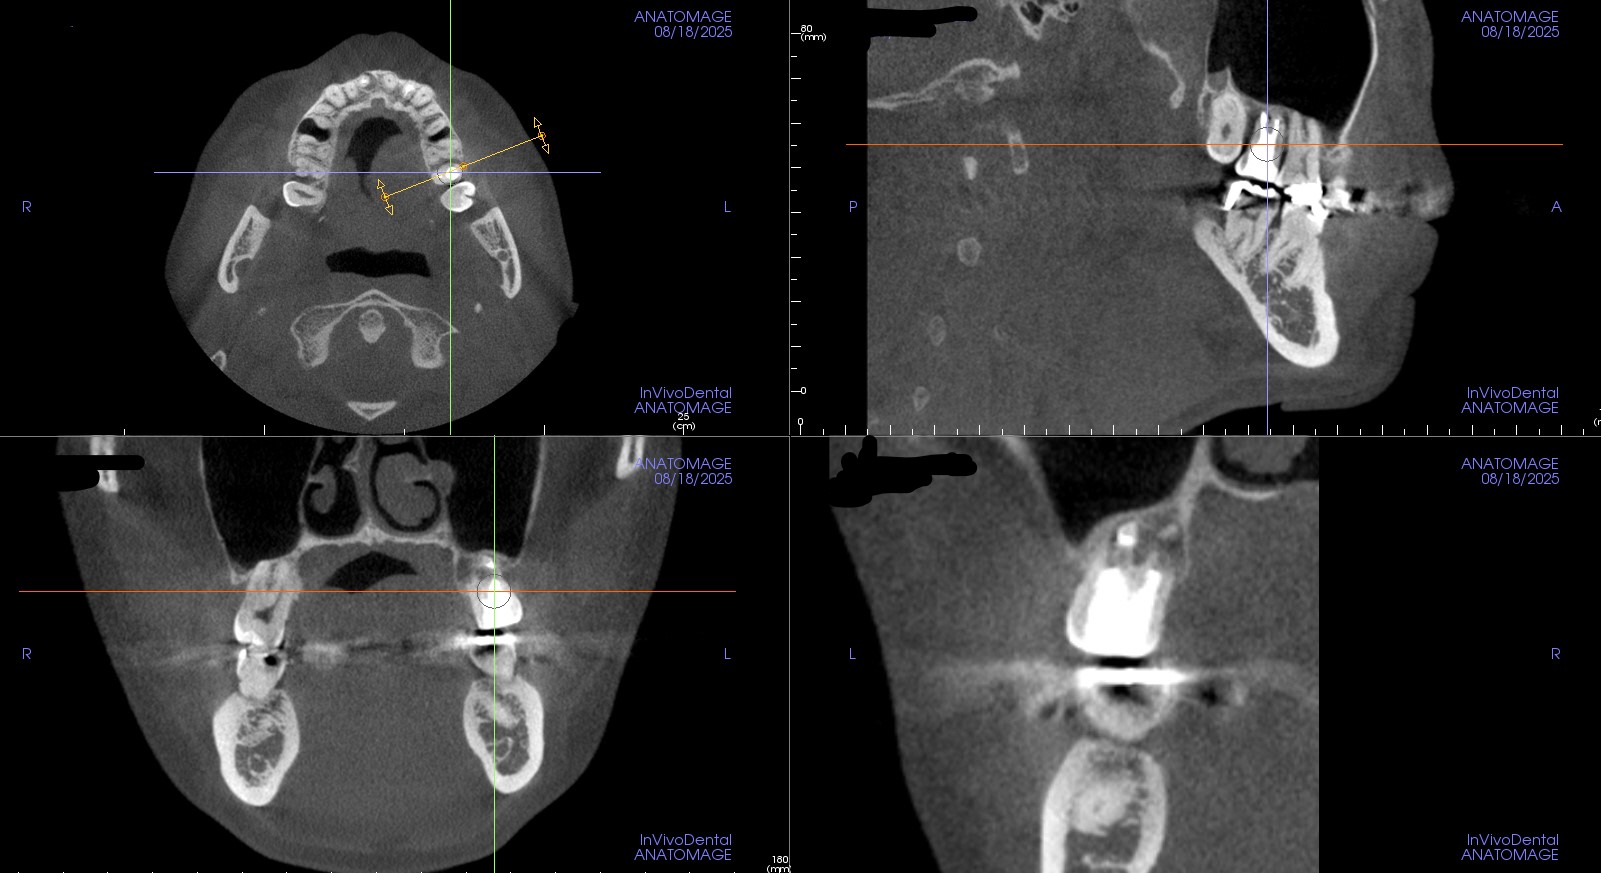

術後

歯の周りに骨が再生しています。